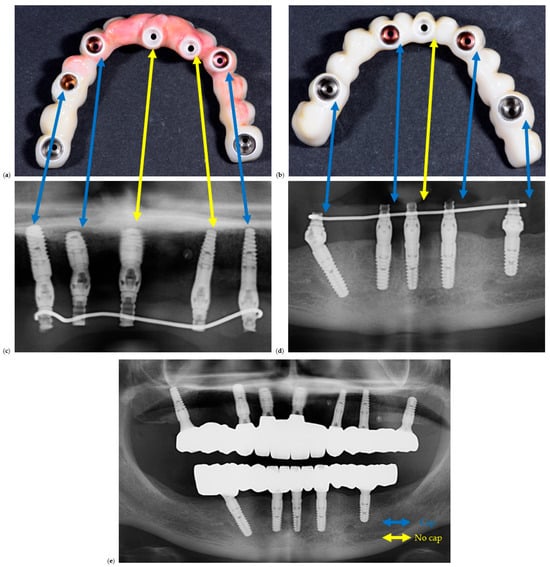

The clinical study was conducted in accordance with the Declaration of Helsinki and approved by the Ethics Committee for Scientific Research of the “Victor Babeș” University of Medicine and Pharmacy, Timișoara (protocol code 16/21.01.2025). All participants provided written informed consent allowing the scientific use of anonymized clinical and radiographic data. The intermediary prosthetic cap components are shown in Figure 1.

Figure 1.

Representative prosthetic caps used as intermediary metallic inserts between the abutment and restoration: (a) occlusal view; (b) lateral view. The image is illustrative of the component concept; the study’s comparative variable was the presence or absence of such a cap [23].

A representative example of restorations fabricated with and without prosthetic caps is illustrated in Figure 2 to demonstrate the restorative configurations compared in this study.

Figure 2.

Clinical and radiographic comparison of screw-retained full-arch restorations fabricated with and without prosthetic caps. (a) Clinical photo of a maxillary full-arch screw-retained restoration, (b) clinical photo of a mandible full-arch screw-retained restoration, (c) section of an OPG corresponding to (a), (d) section of an OPG corresponding to (b). Blue lines are between implant sites with caps, while yellow lines are between implant sites with caps. (e) is the OPG of the final delivered restorations.